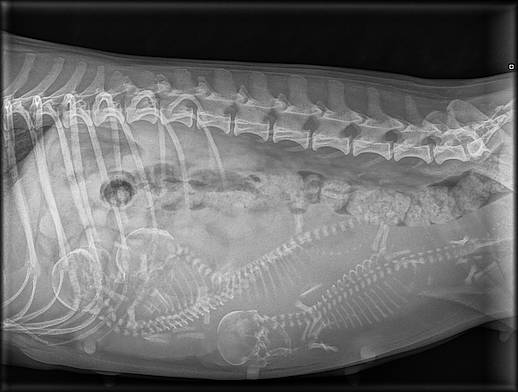

45 Die Knochen verstärken sich.

35 Die Ausbildung der Organe ist abgeschlossen.

Die Föten sehen nun aus wie Hunde.

Kopf und Rumpf sind unterscheidbar.

Das Geschlecht ist bestimmt.

Die Fellfarbe beginnt sich zu entwickeln.

21 Jetzt wären die Embryonen sichtbar bei Ultraschall.

26 Die Embrionen sind etwa walnussgross und sind

gleichmässig im Utenus verteilt.